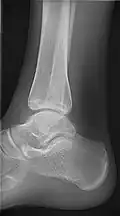

• Ankle - AP/Mortice and Lateral

• Elbow - AP and Lateral. Radial head projections available on request